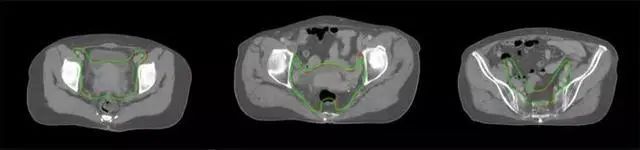

四、放射治療智能勾畫軟件

放射治療,簡稱放療,是治療腫瘤主要手段之一,利用放射線破壞照射區(qū)(靶區(qū))的細胞,使腫瘤細胞停止分裂直至死亡,醫(yī)生通常把放射治療形象的比喻為“打靶”,放療前精準勾畫腫瘤靶區(qū)范圍是腫瘤放射治療的關鍵步驟。傳統(tǒng)的靶區(qū)勾畫醫(yī)生會根據(jù)患者多張CT、MRI影像片憑借經驗進行,比較耗時,治療的病人數(shù)量也有限,且靶區(qū)勾畫缺少行業(yè)統(tǒng)一的規(guī)范和標準,無法達到同質化,勾畫精確度不理想。

技術原理

基于深度學習人工智能的放療靶區(qū)智能勾畫技術和自動計劃技術,基于全面的市場調研和臨床專業(yè)意見,采用獨創(chuàng)的基于小樣本量的人工智能算法,實現(xiàn)放療靶區(qū)和危及器官的快速全自動勾畫。

產品優(yōu)勢

縮短至幾分鐘內便可完成,大幅提升了放療效率,且人工智能平臺完成的靶區(qū)勾畫可基本滿足臨床醫(yī)生需求,專家只需審核時細微調整,可顯著提高靶區(qū)勾畫的規(guī)范化及精準度,讓放療智能化,標準化??筛采w食管癌、鼻咽癌、直腸癌、宮頸癌、肺癌等多種病種。